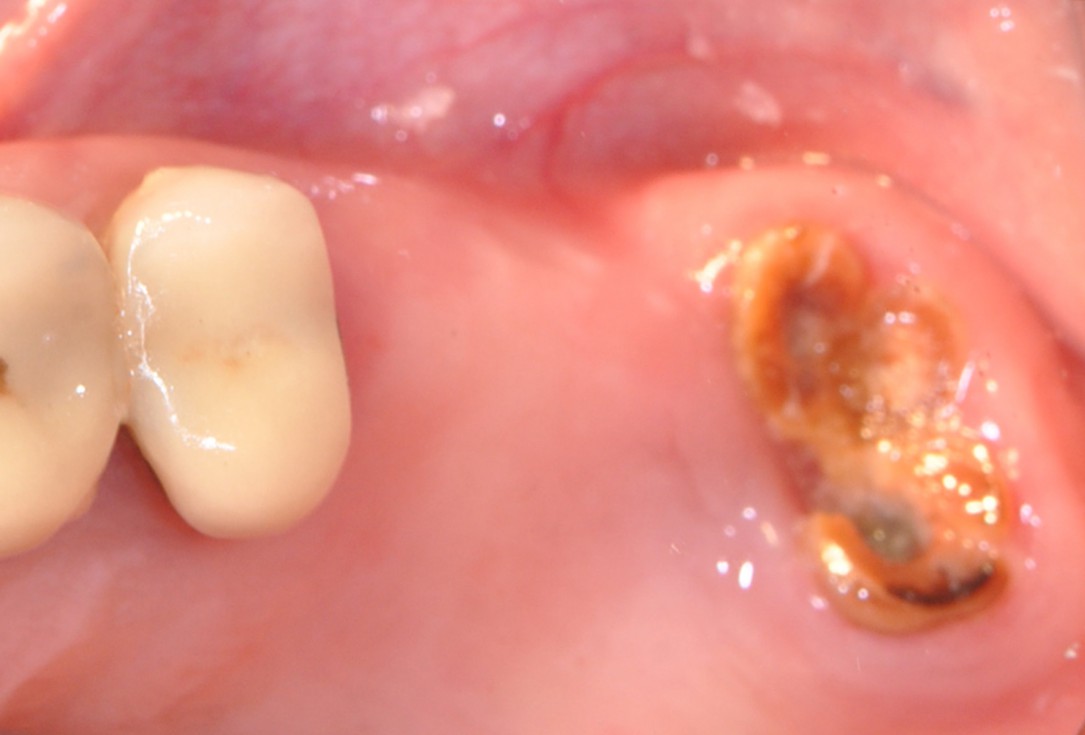

01/16 - Clinical situation of the edentulous distal maxilla before the surgery

One-stage sinus lift - Dr. V. Kalenchuk